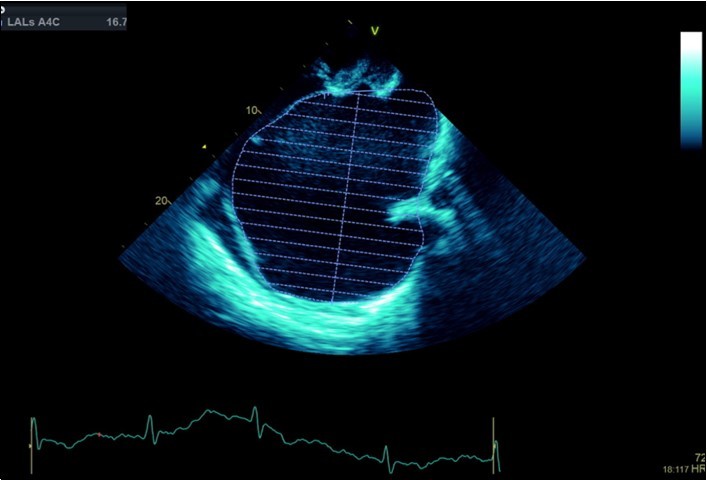

A dramatically dilated left atrium was seen on a TTE (see Figure 2a, Figure 2b, Figure 2c, and Figure 2d). Severe mitral stenosis with associated regurgitation was evident, with a mean gradient across the valve of 11mmHg and a hyperdynamic left ventricle. The left atrial volume measured by Simpson’s biplane method (see Figure 2c) was 2108mL, or 1548.5 ml/m2, based on height 1.55 metres and weight 44 Kg. Normal left atrial volume in a woman is 16 - 34 ml/m21. The computed tomography scan (CT) chest AP view (see Figure 3) is also shown.

Figure 2c.Transthoracic echocardiogram Apical 4C view. Left atrial size estimation by Simpson’s biplane method from apical 4C view.